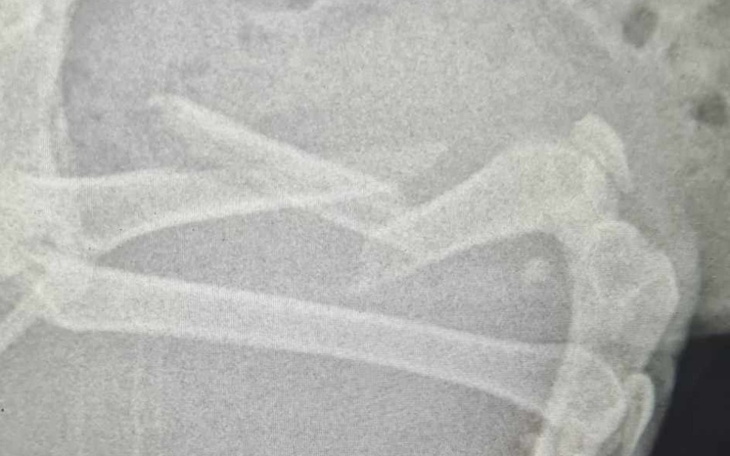

Zebrane pieniądze zostaną wykorzystane na operacje złamanej łapki.